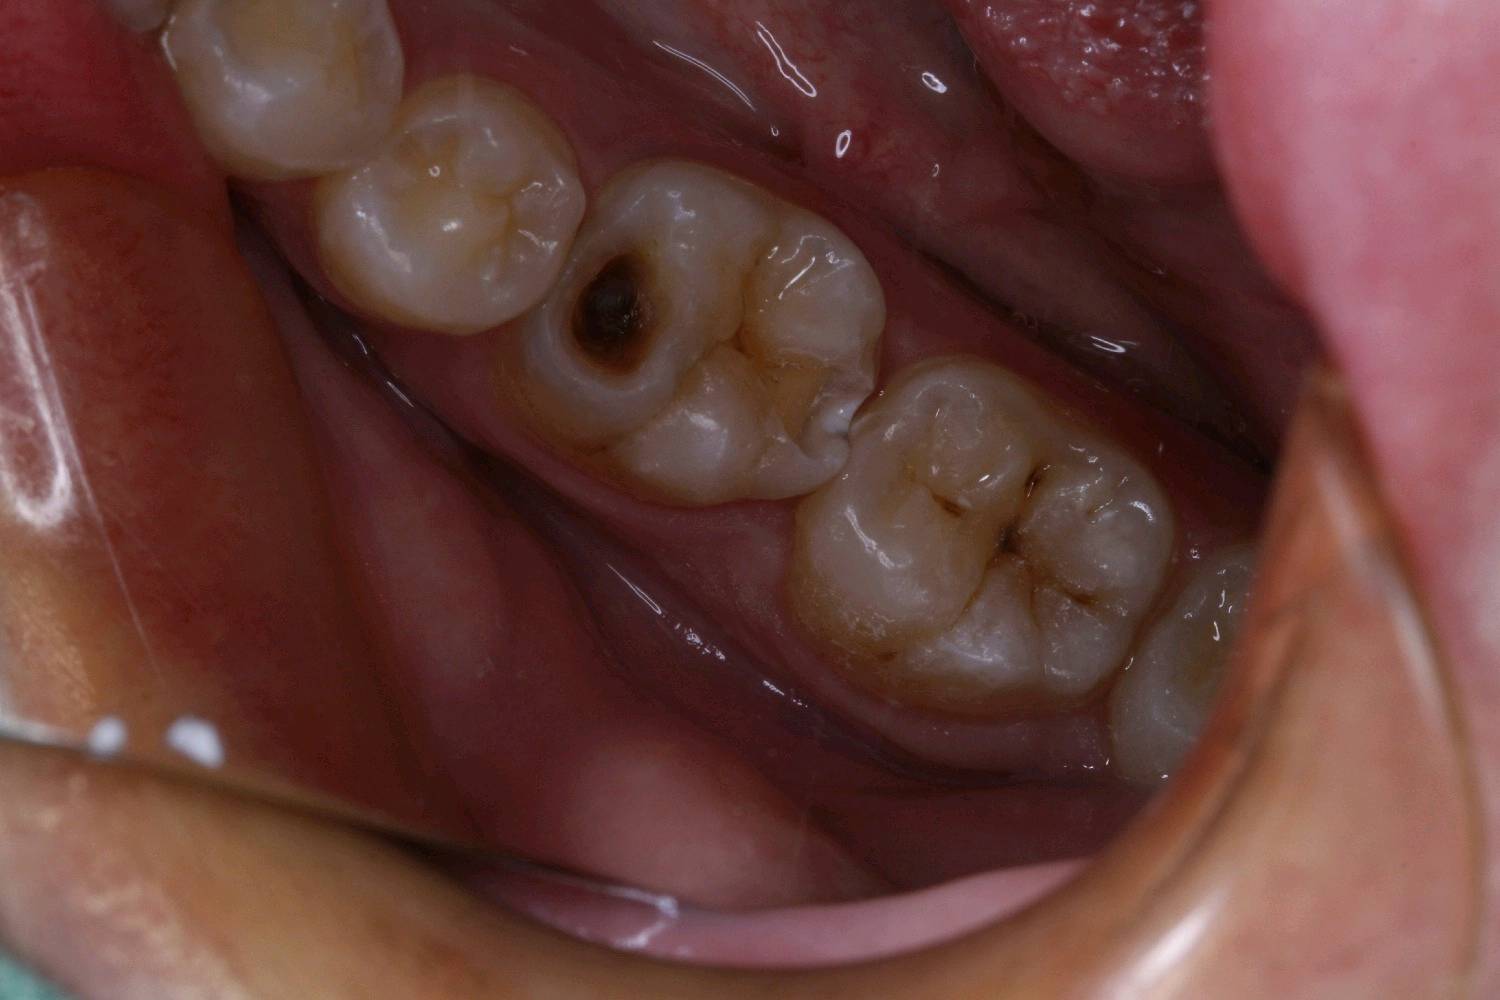

患者男24岁,自述右侧后牙食物嵌塞,无用牙线习惯。检查发现14,15,16,45,46 ,47邻颌面龋坏,探(-),扣(-),冷测正常,龋坏至牙本质中层,余无特殊。

治疗计划:嵌体修复

食物嵌塞为细菌提供了良好的滋生环境,容易导致细菌大量繁殖,产生酸性物质,从而增加蛀牙的风险。最好是用嵌体修复,能更好的恢复牙体的形态和功能。想要有一口好牙齿,做起来也不难。但是,单单口腔清洁这件小事,大多数人都没做好。你以为刷遍了牙齿的每个角落,但可能只刷了一半的牙。刷毛无法有效进入牙缝隙刷牙后仍有食物残渣等残留于牙齿邻面部位导致邻面龋坏。平时不易察觉,需要定期检查,为了更恢复邻接关系,预备制作嵌体,更好的恢复了牙体形态,增加了固位力,恢复正常的邻接关系,可以得到更好洁。基牙预备后,通过德国西诺德 CEREC ,当日完成即可佩戴,患者满意。